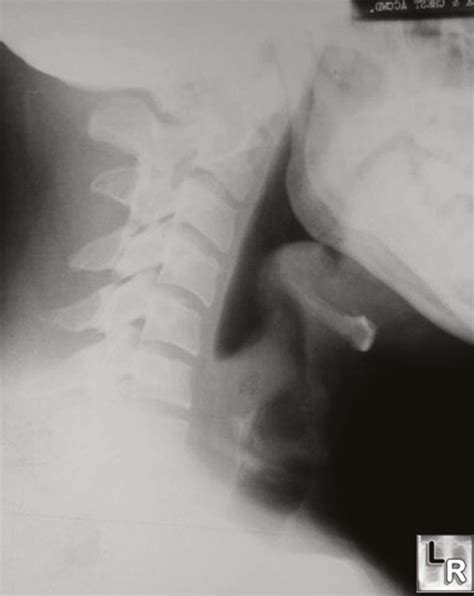

Radiological Identification: The Thumbprint Sign

The Thumbprint Sign Epiglottitis is observed on a lateral soft tissue neck X-ray. Under normal conditions, the epiglottis appears as a thin, wispy shadow. In cases of acute epiglottitis, the inflamed tissue projects posteriorly and superiorly, creating a rounded, dense, soft-tissue opacity that resembles the distal phalanx of a human thumb. Hence, it is commonly called the "thumbprint sign."

While this sign is highly specific, it is not perfectly sensitive. A clinician should never rule out epiglottitis based solely on a "normal-looking" X-ray if the clinical suspicion remains high. The following table highlights key differences in imaging findings between common airway obstructions: